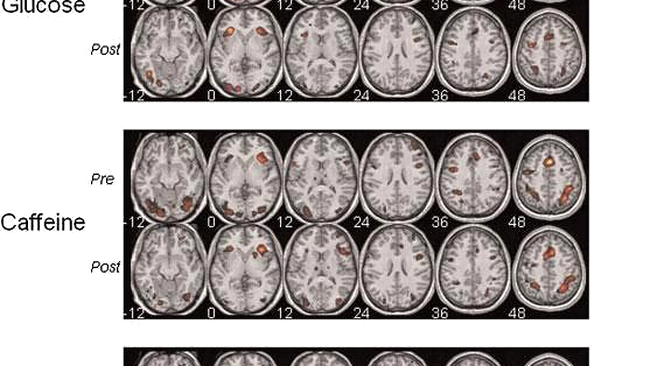

In cadrul unui studiu realizat recent la Universitatea din

Barcelona au fost utilizate imagini RMN pentru a determina

efectul combinatiei de glucoza si cafeina asupra

activitatii cerebrale.

Potrivit cercetatorului Josep M. Serra Grabulosa, acest

mix de substante imbunatateste performanta cognitiva, in

sensul ca sporeste atentia si memoria, prin stimularea zonelor

creierului responsabile pentru aceste functii.

Activitatea cerebrala a participantilor la studiu care

au consumat cafeina si glucoza simultan este mai eficienta,

intrucat creierul acestora are nevoie de mai putine resurse pentru

a junge la performanta cerebrala a subiectilor carora le-au fost

administrate substante placebo.

Culorile contrastante reprezinta

intensitatea activitatii creierului

Concluzia studiului este ca mixul

de glucoza si cafeina are efecte benefice asupra

atentiei si a invatarii, consolidand totodata memoria

verbala.

In cazul consumului acestor substante separat, nu au fost

identificate toate aceste modificari la nivel cerebral.